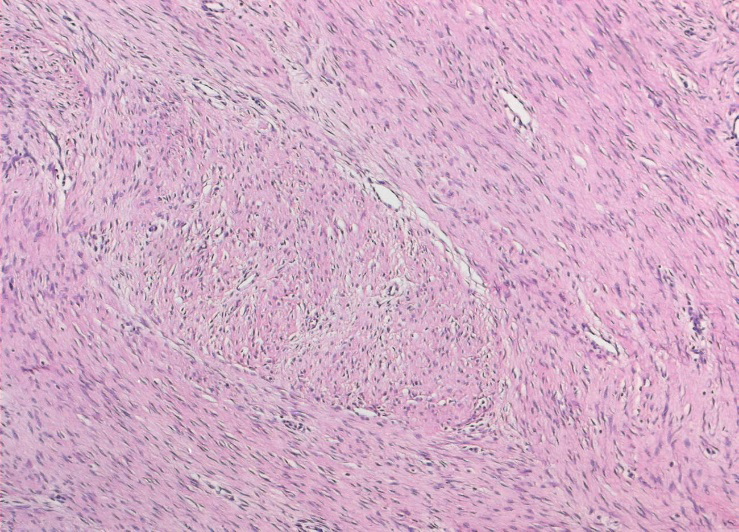

The diagnosis is to be confirmed by biopsy. Microscopically, there is a benign appearance with a well differentiated composition of intersecting bundles of fibroblasts, which are separated by collagen deposits (Figure 2 [Fig. 2]).

Figure 2: Benign appearance with a well differentiated composition of intersecting bundles of fibroblasts, which are separated by collagen deposits (Courtesy of the Institute of Pathology of Leipzig University)